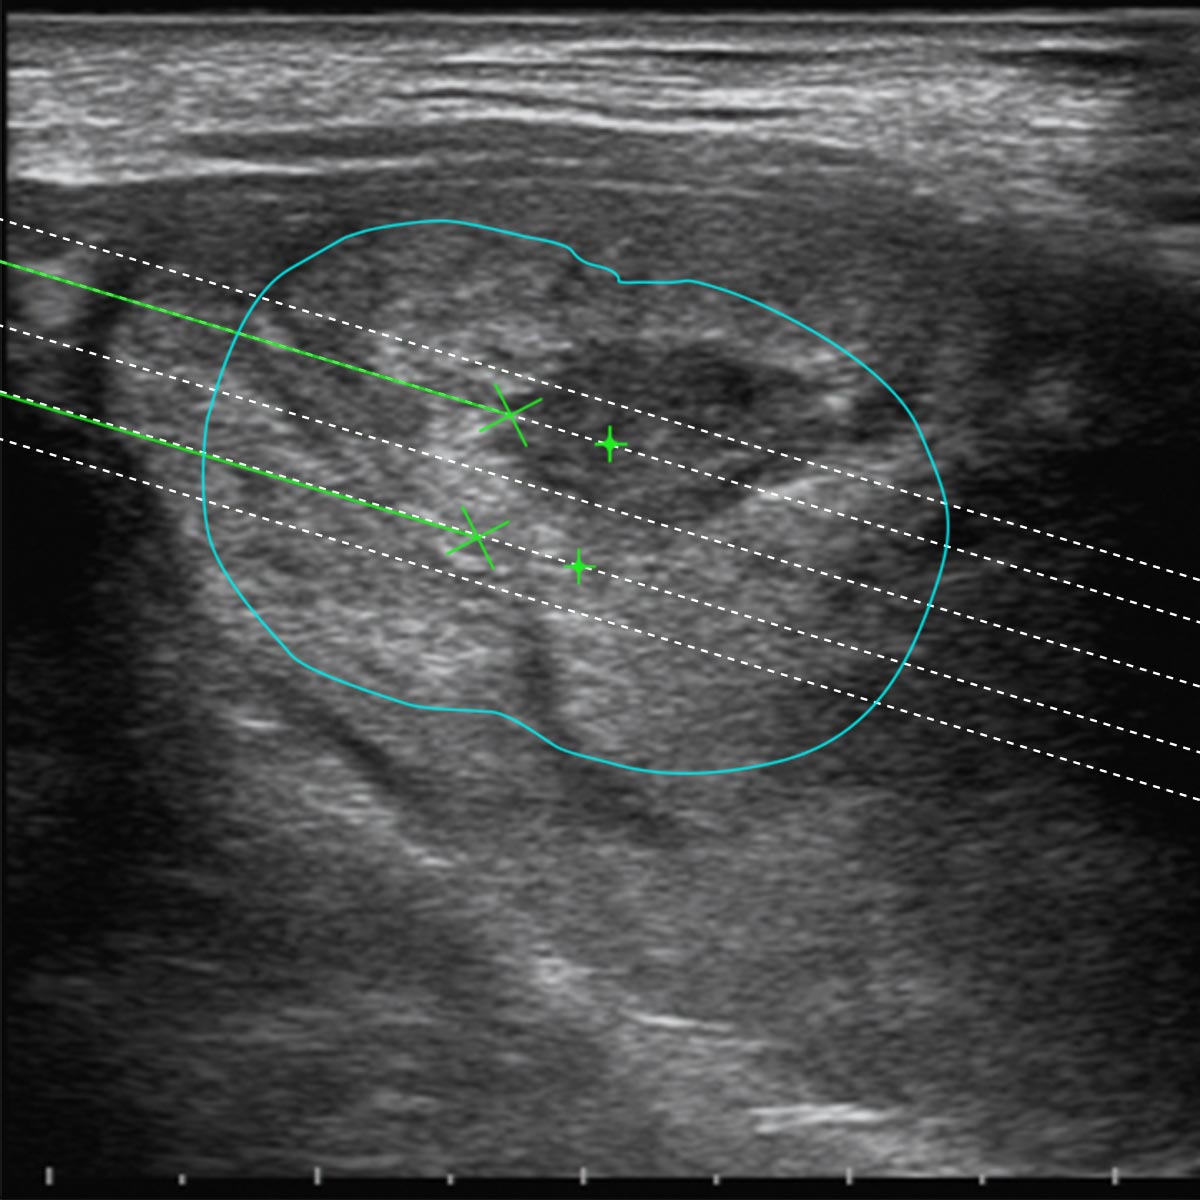

Sistemi Guida degli applicatori e Software Biopsia dedicati

I Sistemi Guida sulle sonde Esaote sono stati sviluppati per ciascuna applicazione per facilitare l’operatore nel posizionamento di più fibre all’interno della lesione da trattare. I Software Biopsia dedicati alla Termoablazione con EchoLaser nella unità US visualizzano le linee guida sullo schermo per ogni differente guida al fine di valutare il miglior posizionamento dell’applicatore in riferimento alla dimensione, morfologia e posizione della lesione.

Il Software di Pianificazione consente all’operatore di valutare la traiettoria di inserimento degli aghi introduttori e l’opzione di trattamento adeguata (numero di applicatori, numero di pull-back, distanza degli applicatori) per ogni caso specifico.

In senso orario:

3. Software di pianificazione pre-trattamento per l’applicazione sul collo